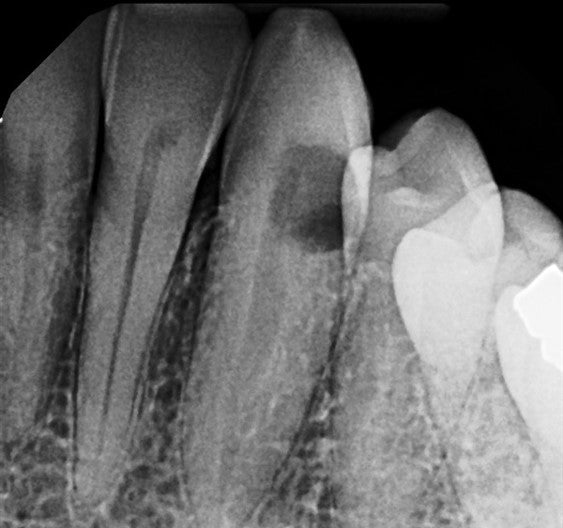

Saving a cental with deep subgingival external root resorption.

Xray Step 1 Resorption included the pulp. Greater Curve Standard Band in place Step 2 I placed the Greater Curve Standard Band before I realized this would be a... Read More